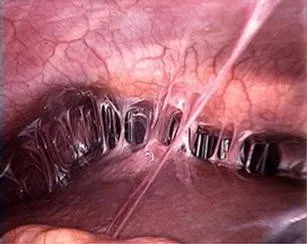

- Fitz-Hugh-Curtis syndrome (perihepatitis; RUQ pain, 'violin-string' adhesions)

⭐ Fitz-Hugh-Curtis syndrome, characterized by perihepatitis and 'violin-string' adhesions between the liver capsule and peritoneum, is a known complication of PID, typically caused by C. trachomatis or N. gonorrhoeae.

- Fitz-Hugh-Curtis syndrome: Perihepatitis (violin-string adhesions) is a specific complication.